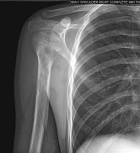

14 year old male with right arm pain after throwing a baseball.

Patient had six months of activity related pain prior to this episode.

Zoom image: Radiological image Radiological image.